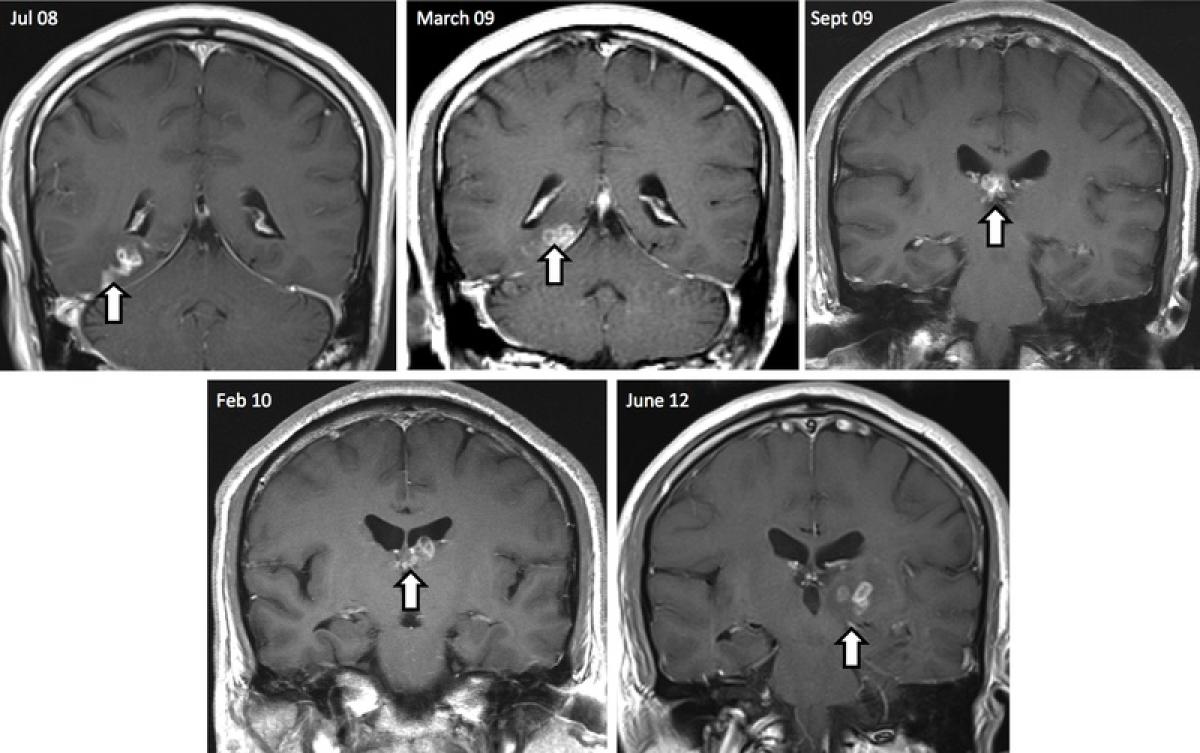

Două scanări cerebrale realizate la interval de 4 ani arată modul în care un vierme lung de 1 cm s-a deplasat prin creierul unui bărbat, înainte de a fi înlăturat în urma unei operaţii.

Viermele se numeşte Spirometra erinaceieuropaei şi este originar din Orientul Îndepărtat, iar cazurile de infestare de acest fel sunt foarte rare, fiind înregistrate numai 300 de cazuri până acum în întreaga lume.

Pacientul este din Marea Britanie şi prima scanare la RMN a fost realizată în anul 2008.

Infestarea cu acest parazit, i-a provocat bărbatului inflamarea țesuturilor, convulsii, dureri puternice de cap și pierderi de memorie.